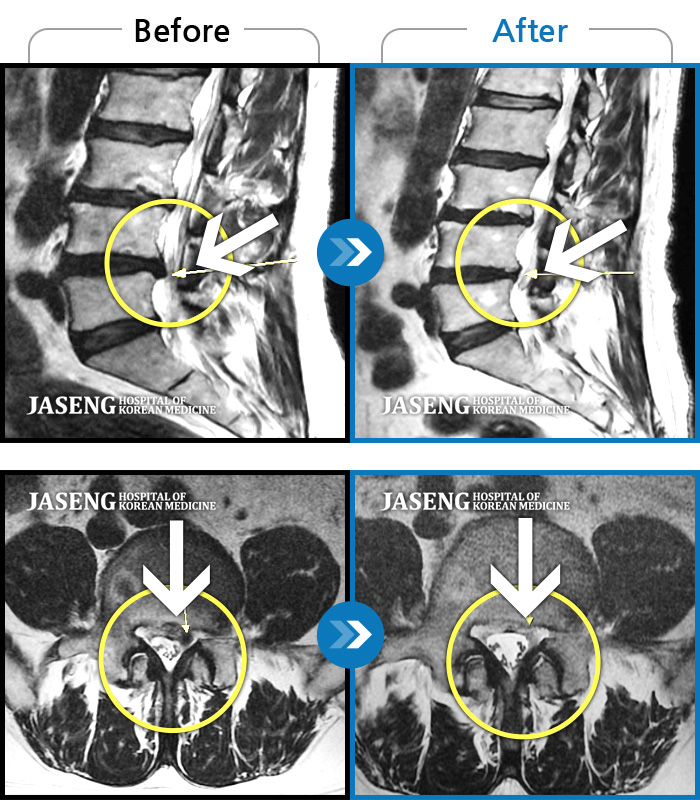

허리디스크

울산 · 정운석 원장

우측 하요추부 통증-우측 둔부-소퇴 후면 통증/비증

촬영시기

2021.08.08 ~ 2021.08.13

2021.08.20